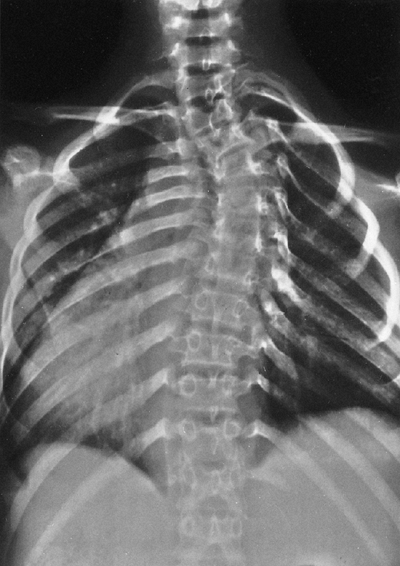

categories: a dystrophic curve and an idiopathic curve. Most curves in

NF resemble idiopathic scoliosis curves.

Their

relation to NF is not understood, and their precise incidence is still

being debated. These curves can be managed like any other idiopathic

curve.

It is associated with deformity of the ribs and vertebrae. The onset is

early in childhood, and it is relentlessly progressive. Curves that

initially appear to be idiopathic in children under age 7 have almost a

70% chance of becoming dystrophic over time, although there may be

subtle clues, for example, mild rib penciling (thinning of the ribs in

a shape similar to a pencil point near the vertebrae), suggesting that

the curve is actually dystrophic. The most important risk factors for

progression are an early age of onset, a high Cobb angle, and an apical

vertebra that is severely rotated, scalloped (concave loss of bone),

and located in the middle-to-lower thoracic area (90).